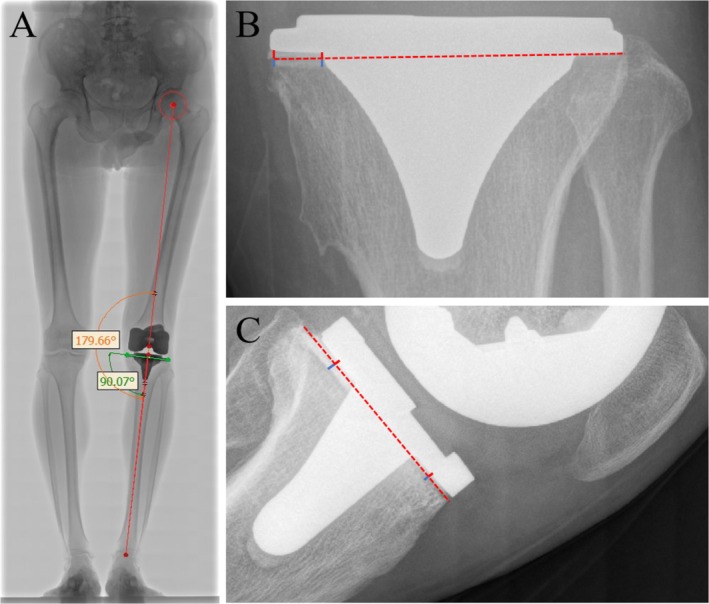

Background: Osteoarthritis (OA) is the most prevalent joint disease in the elderly population, and primary computer-assisted navigation total knee arthroplasty (CA-TKA) remains a critical therapeutic intervention for OA. The presence of physiologic radiolucent lines (RLLs) beneath the tibial base plate following CA-TKA carries significant long-term clinical implications and is regarded as a potential indicator of prosthetic loosening. However, the specific risk factors for RLL development in CA-TKA, despite its theoretical precision advantages, remain poorly understood. This study aimed to characterize the clinical features of physiologic RLLs and identify associated risk factors.

Methods: A retrospective nested case-control study was conducted using a cohort of OA patients who underwent primary CA-TKA between January 2021 and September 2024. Physiologic RLLs were diagnosed according to the 1989 Knee Society Total Knee Arthroplasty Roentgenographic Evaluation and Scoring System. Patients with physiologic RLLs under the tibial base plate at follow-up were assigned to the RLLs group, while controls were matched 1:1 from the cohort based on follow-up time (±14 days). Covariates included age, gender, body mass index, smoking, alcohol consumption, hypertension, diabetes, surgical side, hospital stay duration, operative time, anesthesia type, continuous passive motion use, periprosthetic joint infection, total perioperative blood loss, preoperative/postoperative hip-knee-ankle angle (HKA), tibial cement mantle quality, cement penetration, and perioperative medial proximal tibial angle. Univariate and multivariate analyses were performed to identify risk factors.

Results: The cohort comprised 407 patients, of whom 113 developed physiologic RLLs under the tibial base plate. Univariate analysis identified age, preoperative HKA, tibial cement mantle defects, and cement penetration as statistically significant risk factors (all p < 0.05). Multivariate logistic regression analysis revealed that preoperative HKA (OR = 0.919, 95% CI = 0.876-0.963, p < 0.001), tibial cement mantle defects (OR = 2.638, 95% CI = 1.043-6.668, p = 0.040), and cement penetration (OR = 0.205, 95% CI = 0.126-0.332, p < 0.001) were independent risk factors for physiologic RLLs under the tibial base plate after primary CA-TKA in OA patients. Age was not an independent risk factor.

Conclusions: The overall incidence and clinical characteristics of physiologic RLLs under the tibial base plate after primary CA-TKA were comparable to those reported for conventional TKA techniques. This nested case-control study identified preoperative HKA, tibial cement mantle defects, and cement penetration as independent risk factors for physiologic RLLs, whereas age was not.